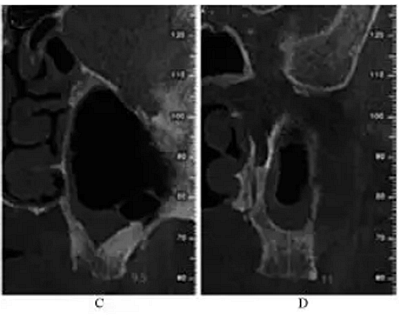

術后5個月,患者無流涕、鼻塞,無其他自覺癥狀。CBCT示:左側鼻甲基本恢復正常,上頜竇高密度影較前明顯減少,仍有少量黏膜增厚。26牙RBH8.1mm,27牙RBH8.4mm(圖4)。擬26~28牙種植修復

圖4 種植前CBCT。注:A,矢狀面;B,26頰舌向切面;C,27頰舌向切面;D,28頰舌向切面。